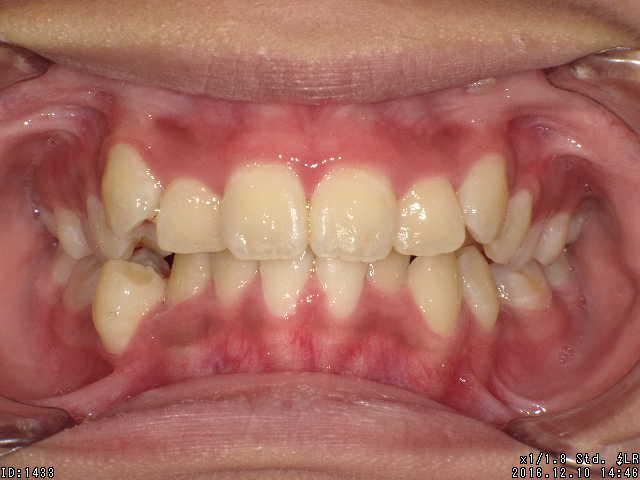

矯正前